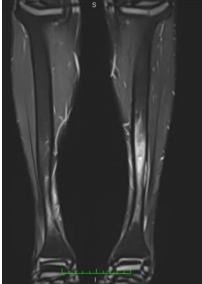

One week later, an MRI (Figure 6) of both legs revealed two cortical lesions within the midshaft of the left tibia, with enhancement and a surrounding periosteal reaction with intramedullary signal changes likely representing an osteoid osteoma. Another suspicious osteoid osteoma was noted in the proximal shaft of the left tibia and the distal shaft of the right tibia, with less enhancement and surrounding inflammatory changes.

Figure 6: Preoperative MRI Scan of the Legs (Coronal View) This coronal MRI scan of the legs demonstrates the detailed soft tissue and bone structure. The image shows a hyperintense signal in the cortex of the left tibia, consistent with the presence of an osteoid osteoma. The surrounding bone marrow edema is also visible, which is typical in active lesions. This MRI provides critical information for the diagnosis and surgical planning of osteoid osteoma.